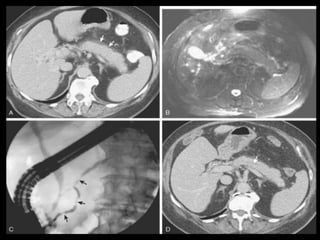

Pâncreas bífido

A CPER tem sido tradicionalmente considerada o

padrão ouro para o diagnóstico dessa condição;

Canulação da papila maior: ducto ventral mais

curto que o normal(1 a 4 cm), não cruza a linha

média e conserva a sua ramificação normal;

Canulação da papila menor: sistema dorsal

permeável drenando o colo, o corpo e a cauda do

pâncreas;

CPRM: 73% de acurácia;

TCMD: pode ser diagnóstica com o uso de

reconstruções multiplanares.